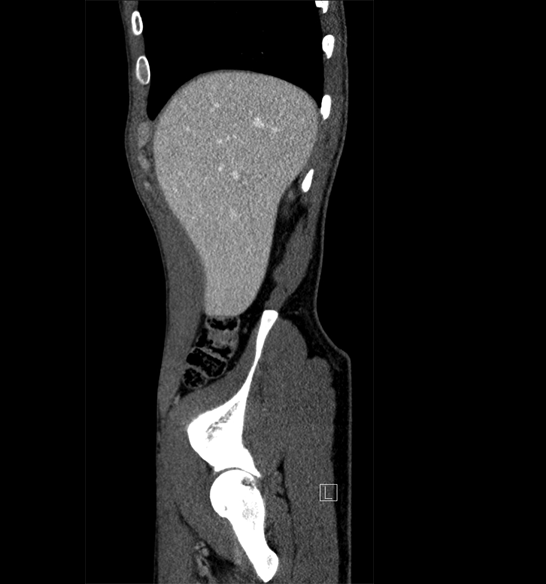

Body

Covers abdominal CT anatomy.